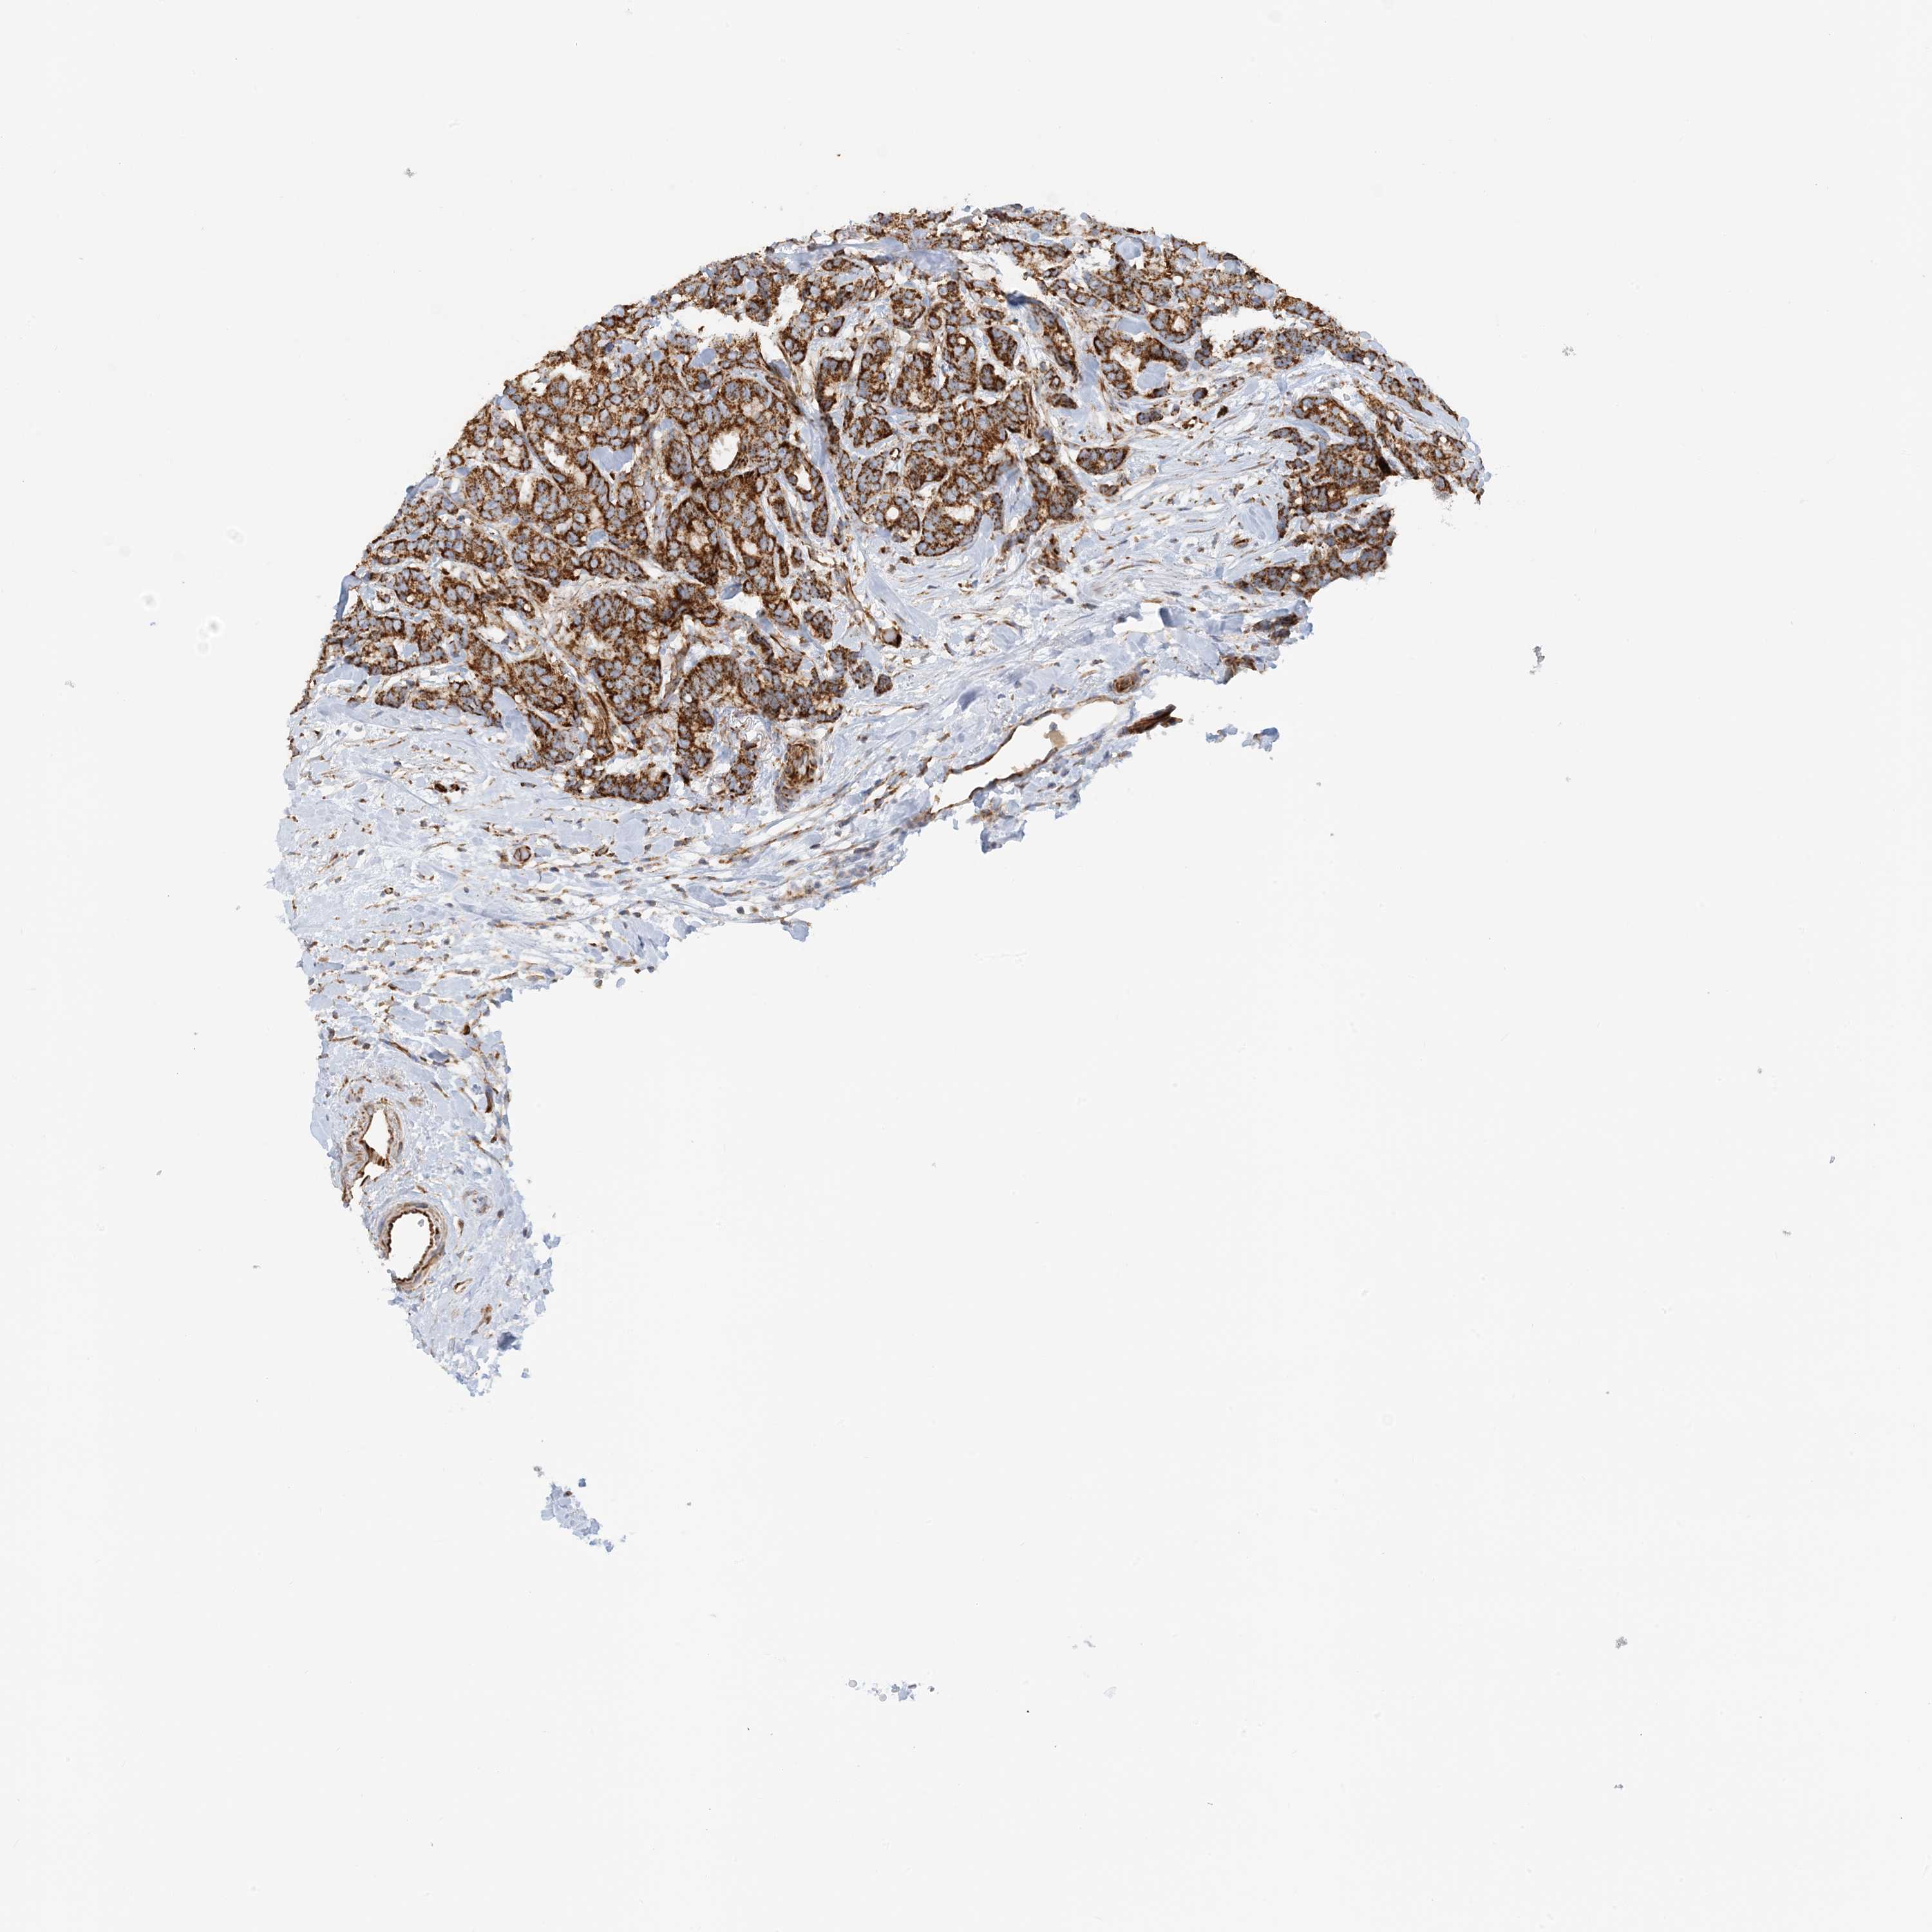

CANCER BREAST CANCER Show tissue menu

BRCA TCGA BRCA VALIDATION PROTEIN EXPRESSION

ANTIBODIES

AND

VALIDATION